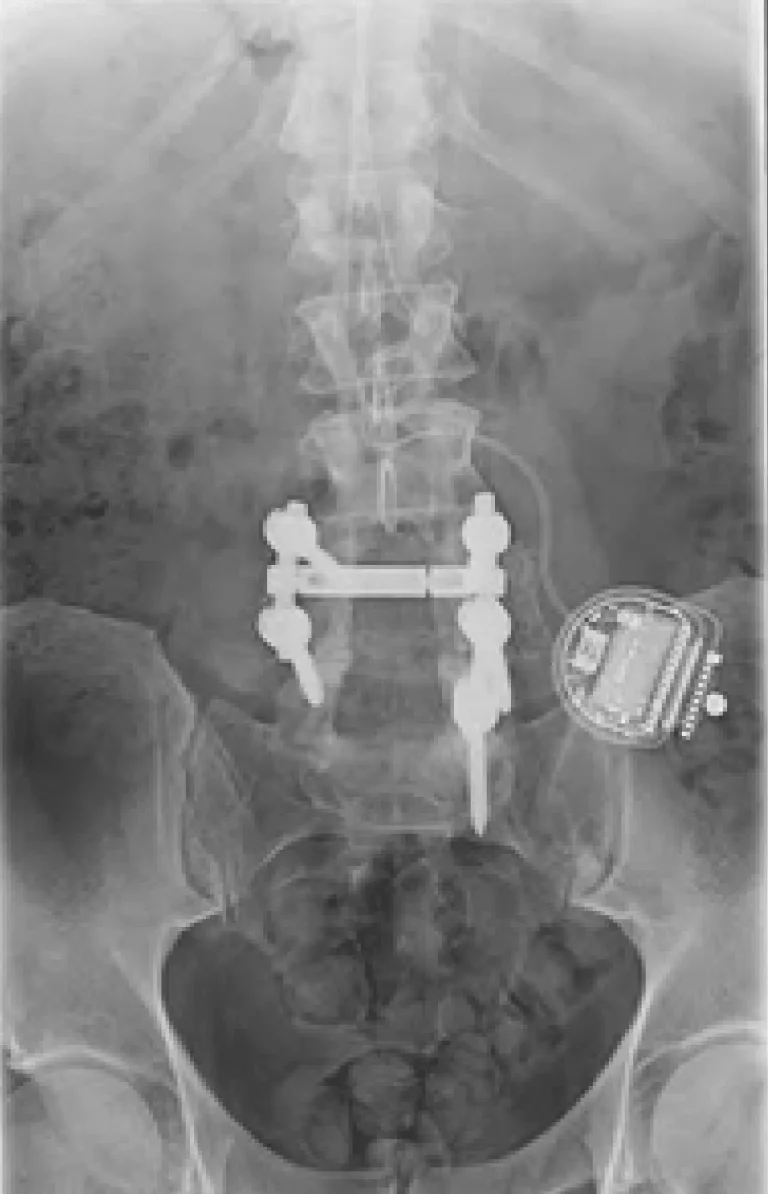

X-ray of a lower spine with metal implants and a medical device on the right side.

Back Pain Gets Worse